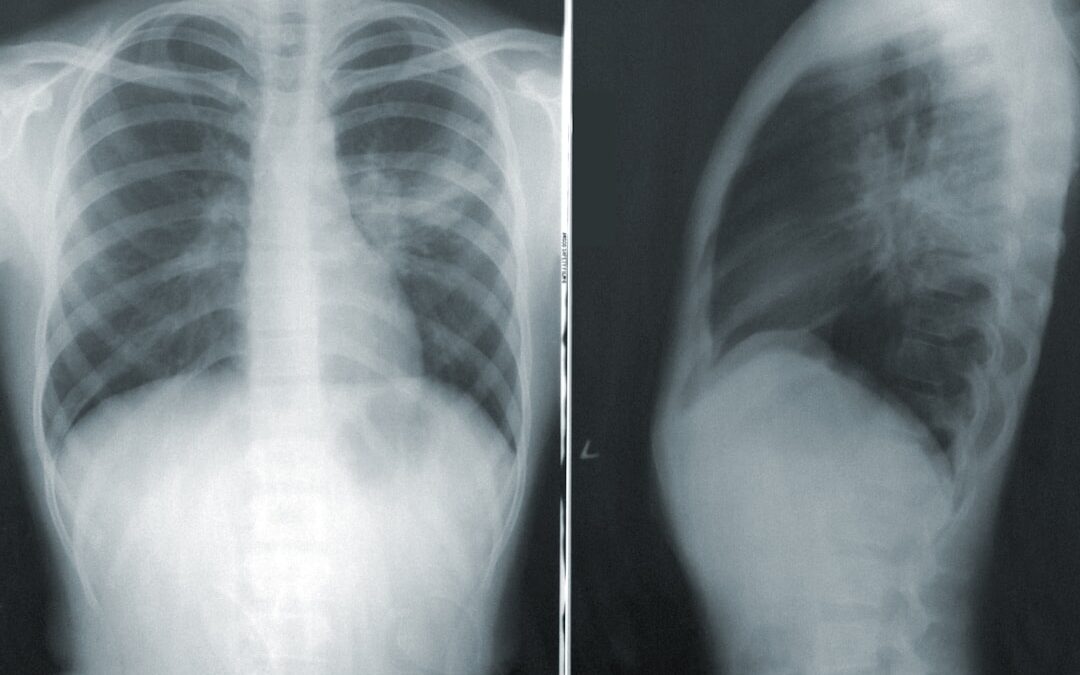

A hasnyálmirigy rák diagnózisa több lépésből áll. Az orvosok általában részletes kórtörténetet vesznek fel, és fizikális vizsgálatot végeznek. Ezt követően képalkotó vizsgálatokra van szükség, mint például ultrahang, CT-vizsgálat vagy MRI, amelyek segítenek az elváltozások lokalizálásában és méretének meghatározásában.